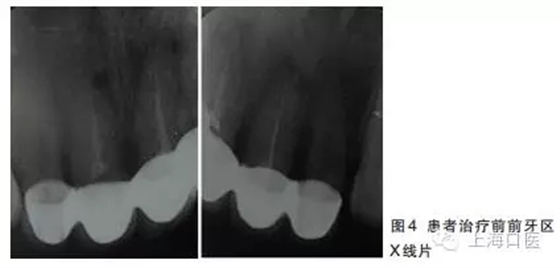

12~22烤瓷聯(lián)冠修復(fù),冠邊緣不密合,齦緣外形不協(xié)調(diào),牙齦紅腫,22烤瓷冠崩瓷。根管治療不完善,牙齦根尖部位有瘺管,X線影像顯示11、21根尖有陰影。

董艷梅教授:修復(fù)前如有以下情況,應(yīng)考慮進行根管再治療:①X線片顯示前次根管治療不完善;②X線片顯示患牙根尖周新增病變或根尖周病變范圍擴大或未見縮小;③患牙在前次根管治療后長期有癥狀或臨床體征。